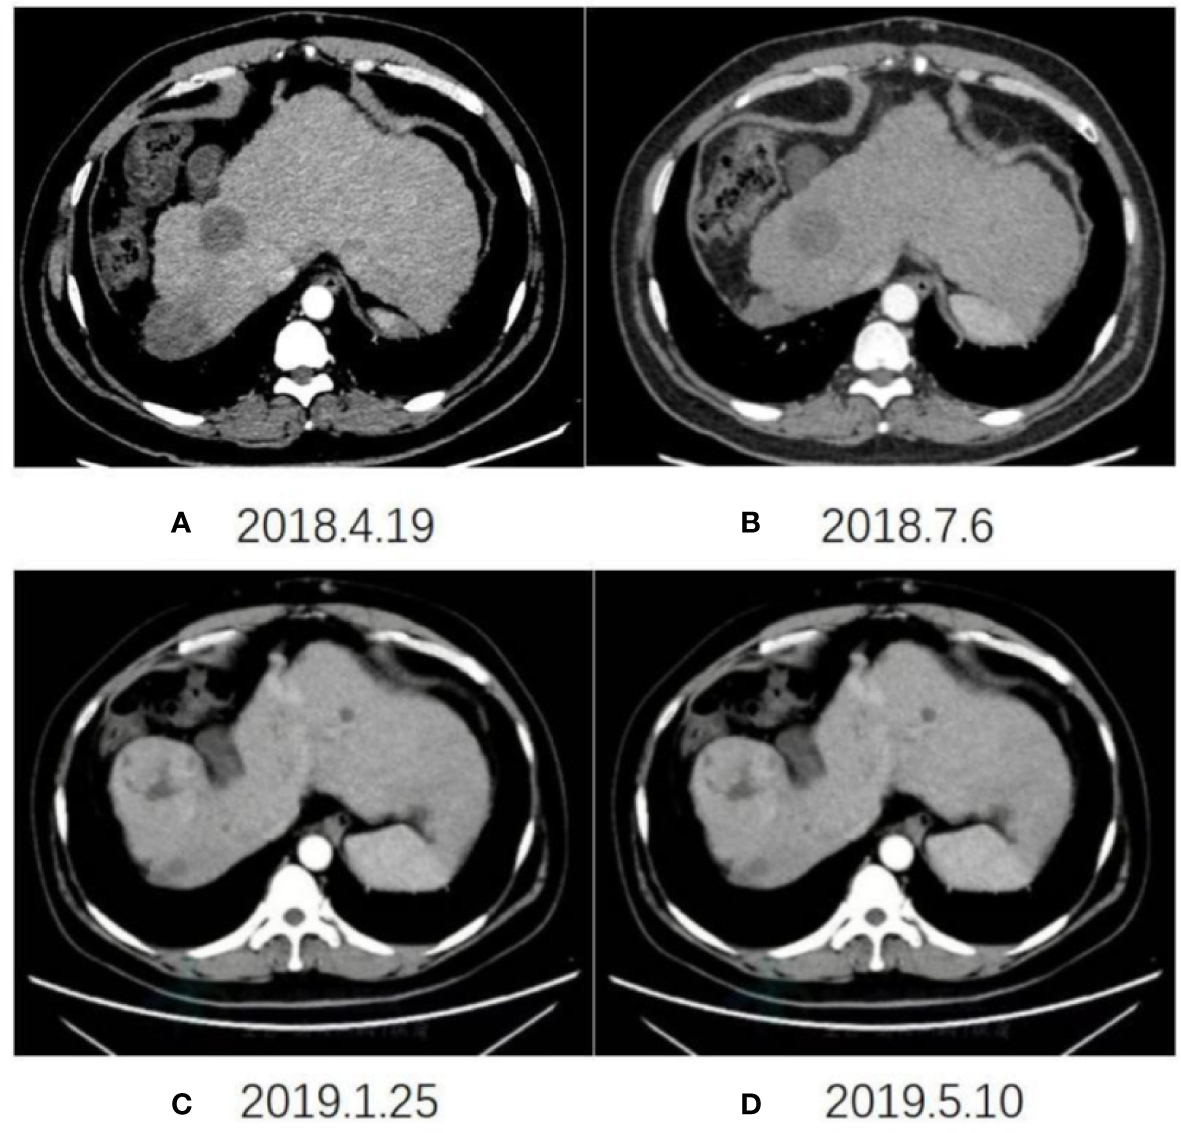

The imaging examination (abdominal ECT) results of the patient are shown in Figure 2, and the foci size in the liver during the treatment and at different post-treatment time points by the abdominal ECT are shown in Table 1, while the changes between the prior-treatment and post-treatment MRI pictures of abdomen are shown in Figure 3A.

Figure 2

Changes in abdominal ECT after the initial CAR T-cell therapy on April 19, 2018 (A), July 6, 2018 (B), January 25, 2019 (C), May 10, 2019 (D), respectively.

Table 1

| DATE | Right anterior lobe | Right posterior lobe |

|---|---|---|

| 2018-4 | 34mm | 41mm |

| 2018-7 | 46mm | 37mm |

| 2018-12 | 56mm | 33mm |

| 2019-1 | 66mm | 30mm |

| 2019-5 | 70mm | 26mm |

The changes in foci size in the liver at different time points during and after treatment by abdominal ECT.